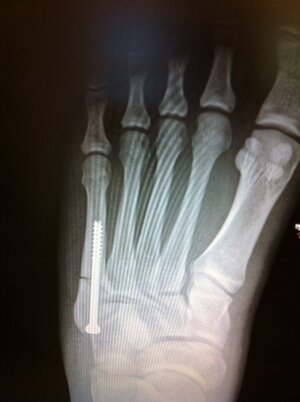

As some of you know I broke my foot on April 15th skiing. My left foot stayed locked in the foothold and the ski slid out from underneath me. My foot ended up rotating into the side of the tray and broke from the impact. I thought that it wasn't a big deal I would be out for 4-6 weeks and then back on the water. I was wrong! After meeting with my doctor he sent me to an orthopedist. On April 20th I met with the orthopedist he took a look at the X-ray and immediately said that I have a Jones fracture. That's when I knew I was in trouble. We scheduled the surgery on April 28th and they ended up putting a screw in my foot. Now I am out at least until August and that is me being hopeful because this break supposedly takes forever to heal.